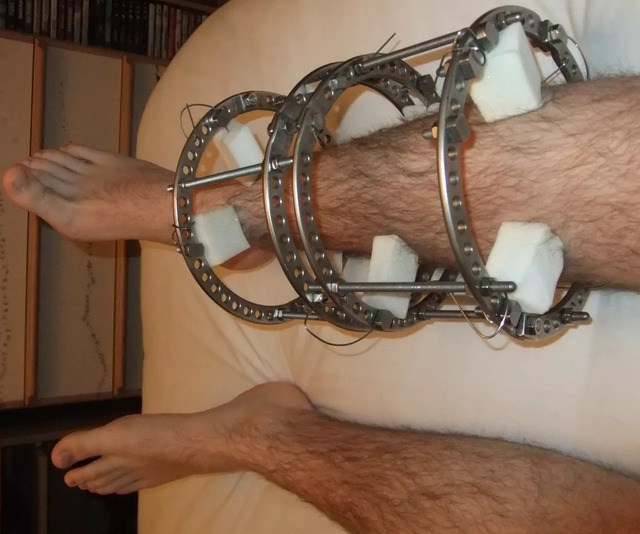

Thiết bị Ilizarov cũng có thể được sử dụng để ổn định xương trong quá trình chữa lành sau các ca phẫu thuật gãy xương phức tạp.

Các ca phẫu thuật này cũng mang tính xâm lấn cao. Về cơ bản, các bác sĩ sẽ bẻ gãy chân, và sau đó thay vì đặt nó về vị trí cũ, họ gắn thêm một “giàn giáo” mang phong cách thời trung cổ vào chân, thứ hay được gọi là khung Ilizarov. Các đinh ghim trên nẹp được vít vào và gắn vào xương để giữ chân thẳng hàng, nhưng cũng đủ khoảng trống để tạo điều kiện cho xương mới phát triển. Các bệnh nhân thường nằm liệt giường trong nhiều tháng nhưng cuối cùng vẫn sẽ đi lại được.

Một số bác sĩ phẫu thuật ngày nay vẫn thực hành theo quy trình và thiết bị từ thời Ilizarov. Tuy nhiên, một số người như tiến sĩ Debiparshad đã áp dụng một số phương pháp tương đối mới, chỉ được phát triển trong 5 năm qua. Nó có lợi thế hơn so với việc sử dụng khung Ilizarov, trong đó điểm rõ ràng nhất là loại bỏ việc tạo ra nhiều vết thương hơn mức cần thiết. Với tất cả các thao tác cơ học đều nằm trong chân và được điều chỉnh bằng từ tính, nên phương pháp mới ít có khả năng gây ra nhiễm trùng từ các vết loét do các chốt của khung Ilizarov gây ra.